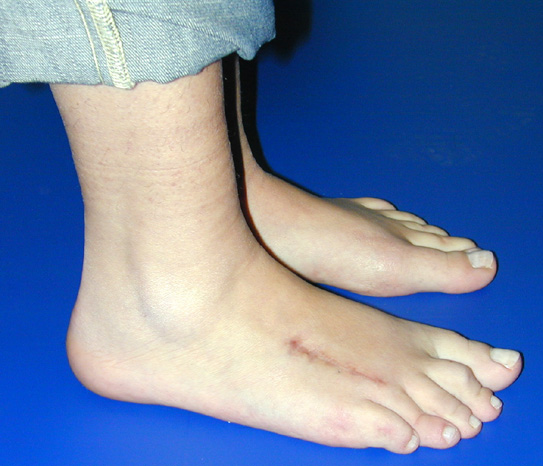

El parmağı (metakarp) ve ayak parmağı (metatars) kısalıkları doğuştan tek başına, geniş bir sendrom grubuyla birlikte, travma sonrası, Freiberg hastalığı (avasküler nekroz) sonrası görülebilir.

Doğuştan metakarp ve metatars kısalığının görülme sıklığı 1/1000’den azdır. Kadınlarda erkeklere göre 5 kat daha fazla görülür ve sıklıkla (%72) iki taraflıdır. En sık 4. parmak tutulur. Bu tür olgularda sorunun nedeni tam olarak bilinmemekle brlikte deformitenin genellikle epifiz plağının erken kapanmasından kaynaklandığı düşünülmektedir.

Metakarp kısalığında kozmetik görünümün bozulması ve dominant elin kullanımı sırasında yorulma, metatars kısalığında ise kozmetik haricinde metatarsalji, kısa parmağın dorsale kayması sonucu deformite oluşması, plantar yönde açılanması sonucu ağrı ve bası ülserleri, ve ayakkabı giymede zorluk nedeniyle ameliyat gerekebilir.

Doğuştan metakarp ve metatars kısalıklarının redavisi için pek çok teknik tanımlanmakla birlikte en çok akut uzatma sonrası kemik uçlarına greft konması ve distraksiyon osteogenezi (kallotasis) kullanılmaktadır. 1 cm.den daha fazla uzatma gereken olgularda kallotasis yöntemi önerilmektedir. Kliniğimizde de metatars ve metakarp uzatma için unilateral eksternal fiksatör ve sirküler eksternal fiksatör yardımıyla distraksiyon osteogenezi yöntemi tercih edilmektedir.